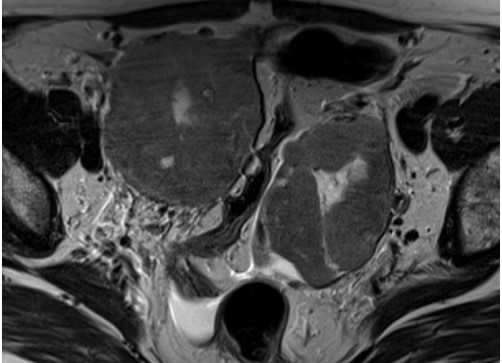

МРТ малого таза, аксиальная плоскость. Объемные кистозно-солидные образования яичников с четкими и неровными контурами, неправильно овальной формы.